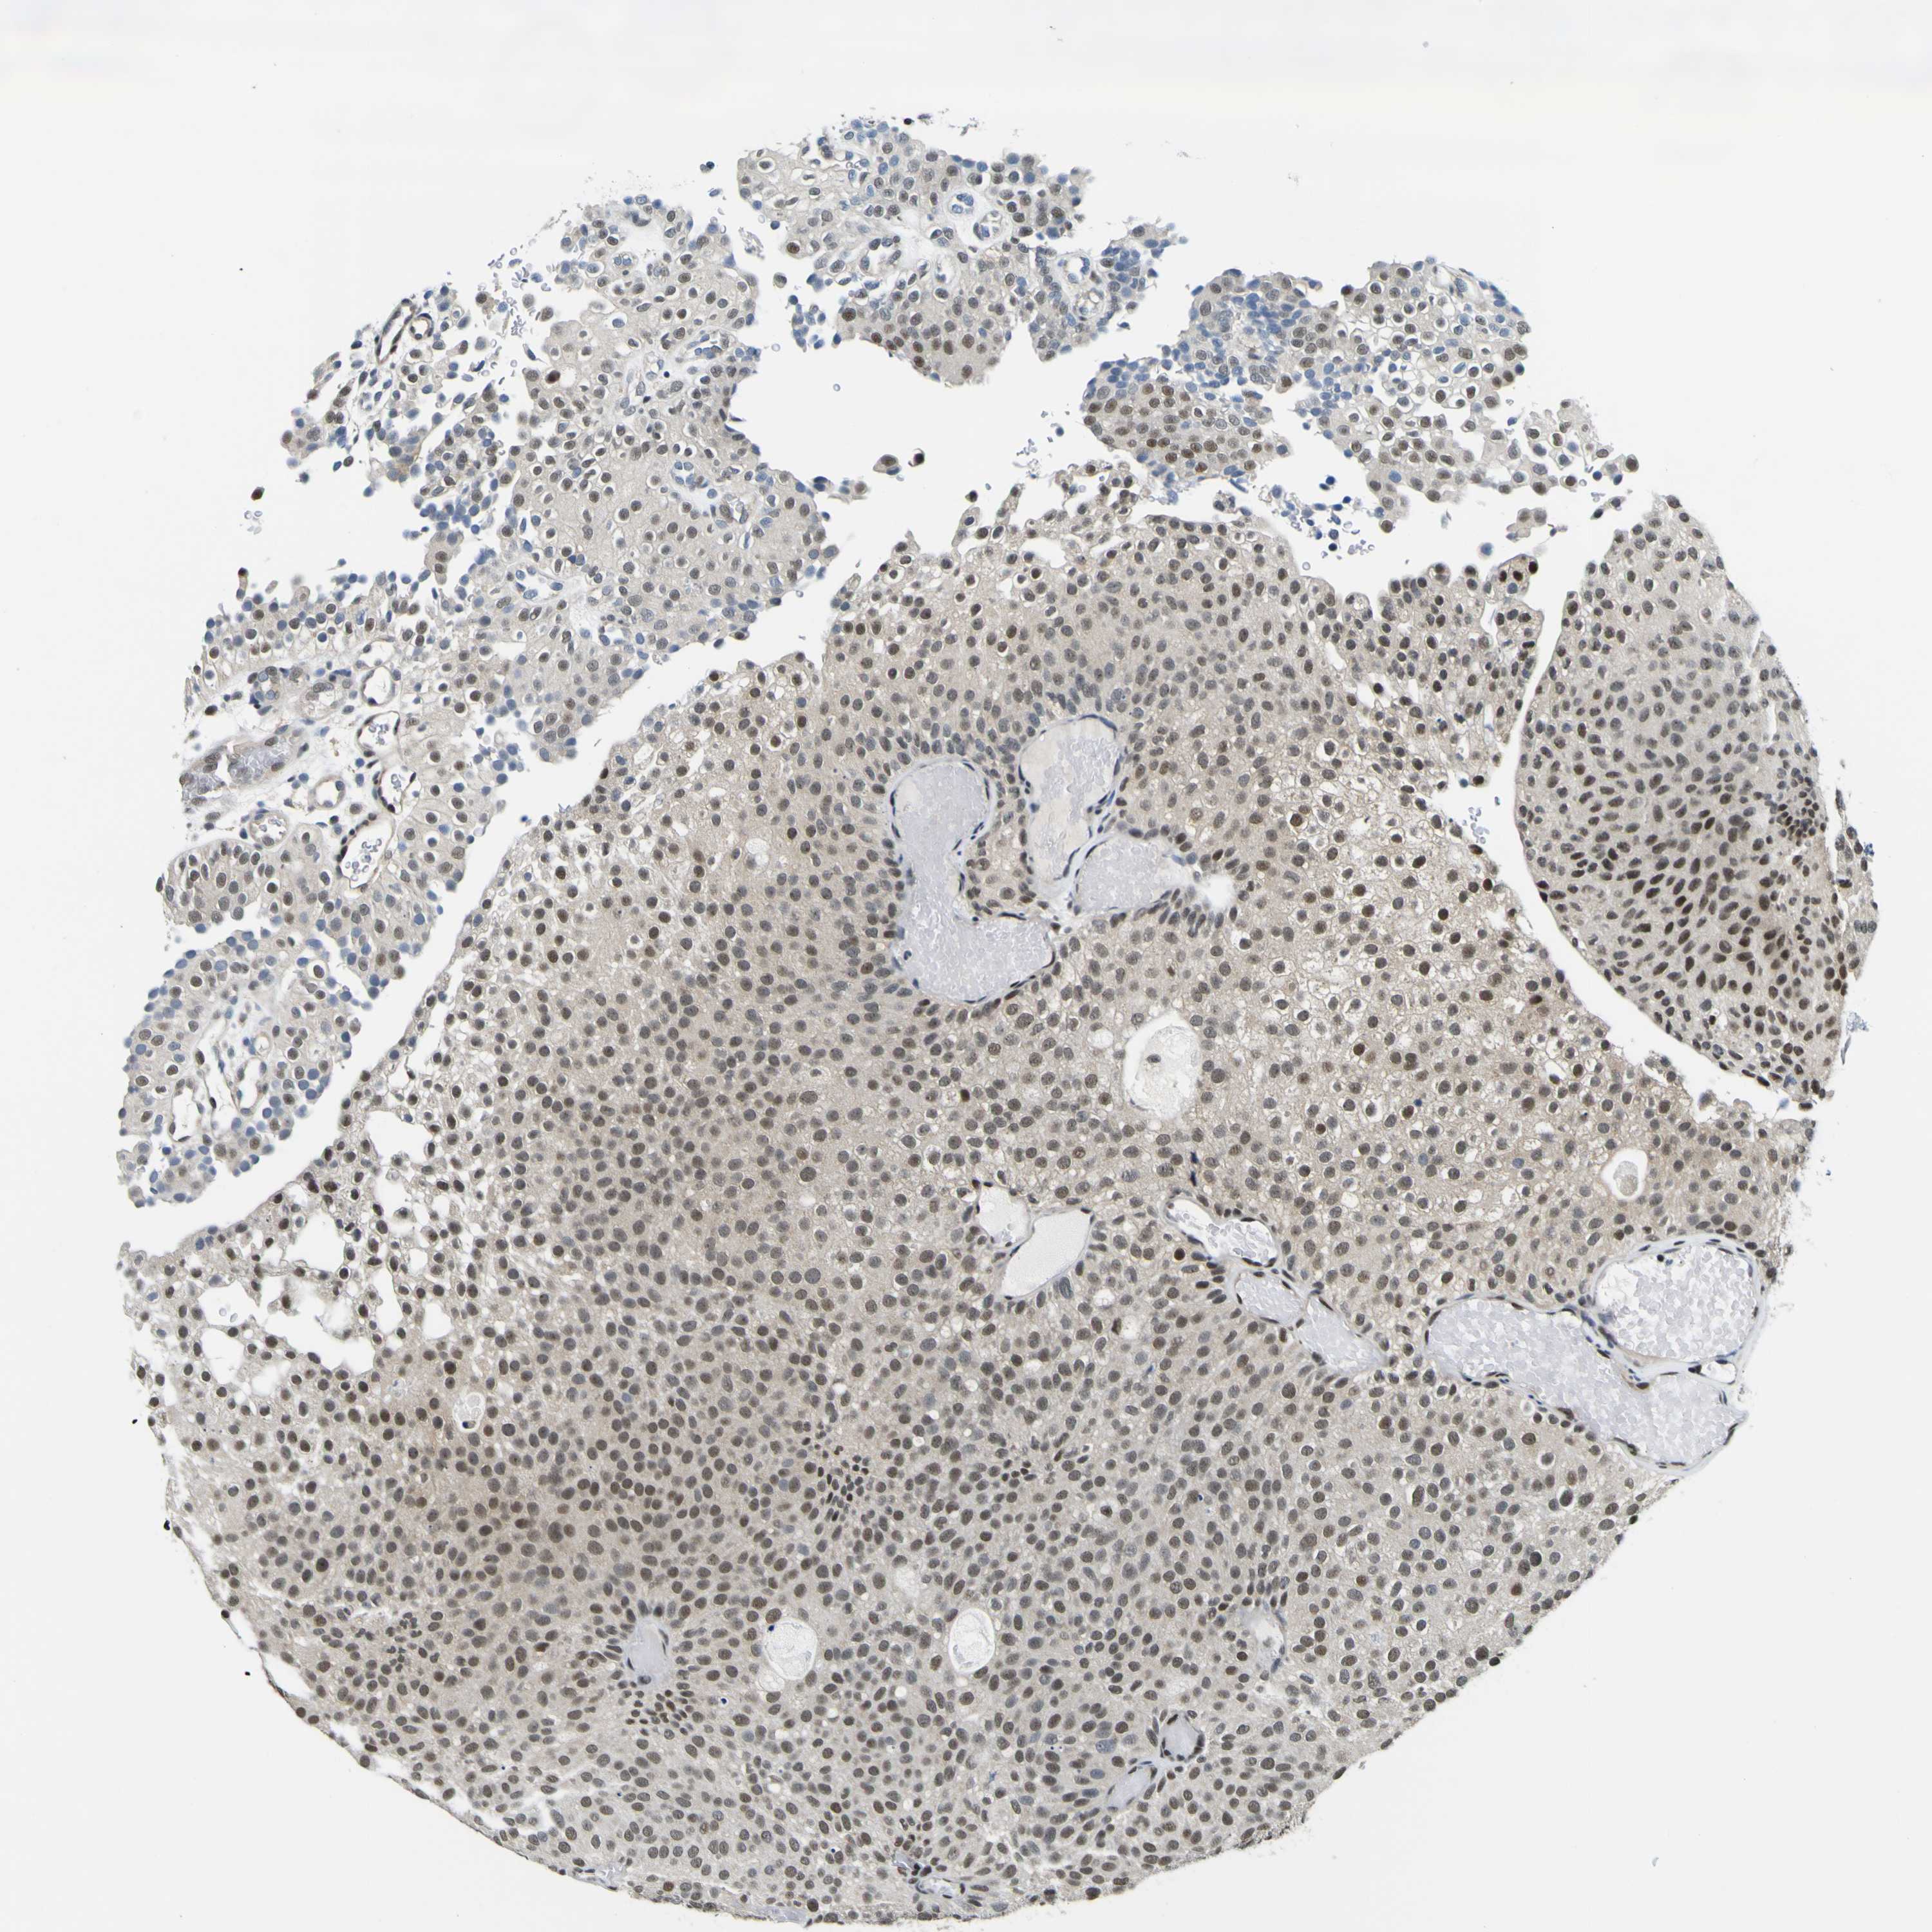

UROTHELIAL CANCER - Protein expressioni

A mouse-over function shows sample information and annotation data. Click on an image to view it in a full screen mode. Samples can be filtered based on level of antibody staining by selecting one or several of the following categories: high, medium, low and not detected. The assay and annotation is described here.

Note that samples used for immunohistochemistry by the Human Protein Atlas do not correspond to samples in the TCGA dataset.

Antibody stainingi

Antibody staining in the annotated cell types in the current human tissue is reported as not detected, low, medium, or high, based on conventional immunohistochemistry profiling in selected tissues. This score is based on the combination of the staining intensity and fraction of stained cells.

Each image is clickable and will lead to virtual microscopy that enables deeper exploration of all samples and also displays staining intensity scores, fraction scores and subcellular localization as well as patient and tissue information for each sample.

Antibody HPA001853

Antibody HPA012292

Antibody CAB000330

Staining

High

Medium

Low

Not detected

Intensity

Strong

Moderate

Weak

Negative

Quantity

>75%

75%-25%

<25%

None

Location

Nuclear

Cytoplasmic/membranous

Cytoplasmic/membranous,nuclear

Urothelial carcinoma, High grade

Urothelial carcinoma, Low grade